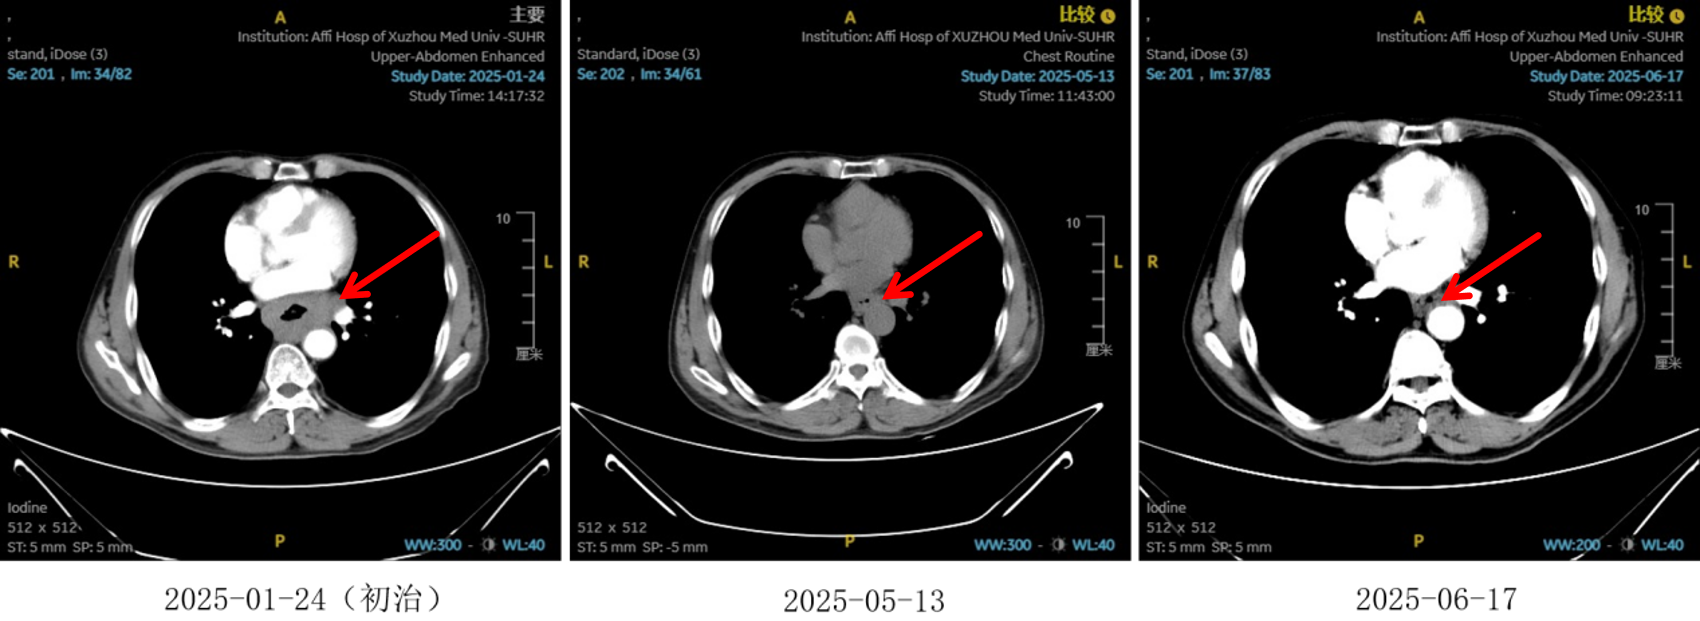

2025-01-22:患者行胃镜及病理检查确诊为食管鳞状细胞癌,CT提示病变位于胸中下段,伴纵隔、左肺门及胃小弯旁多发淋巴结转移,临床分期为cT4N2M0,属于局晚期食管癌。

图1:初治影像学 [图左:食管胸中下段管壁增厚,强化不均,较厚处管壁约17mm,边缘模糊,病灶局部与邻近大血管、气管壁分界不清。图右:纵隔内(3P、4、7)、左肺门及胃小弯旁示多发增大淋巴结影,部分融合,强化不均,较大者大小约18mm×15mm。]

图2:2周期化疗联合抗血管治疗后食管癌病灶对比

图3:2 周期化疗联合抗血管治疗后淋巴结对比

图5:4、6周期化免靶后食管癌病灶对比

图6:4、6周期化免靶后淋巴结对比

疗效评估

治疗2周期后,食管壁厚度由17mm降至15mm,淋巴结由18mm×15mm缩小至16mm×13mm;4周期后,食管壁进一步缩至12mm,淋巴结明显减少;6周期后,食管壁仅余10mm,纵隔内仅见小淋巴结影,疗效评估“接近CR”。